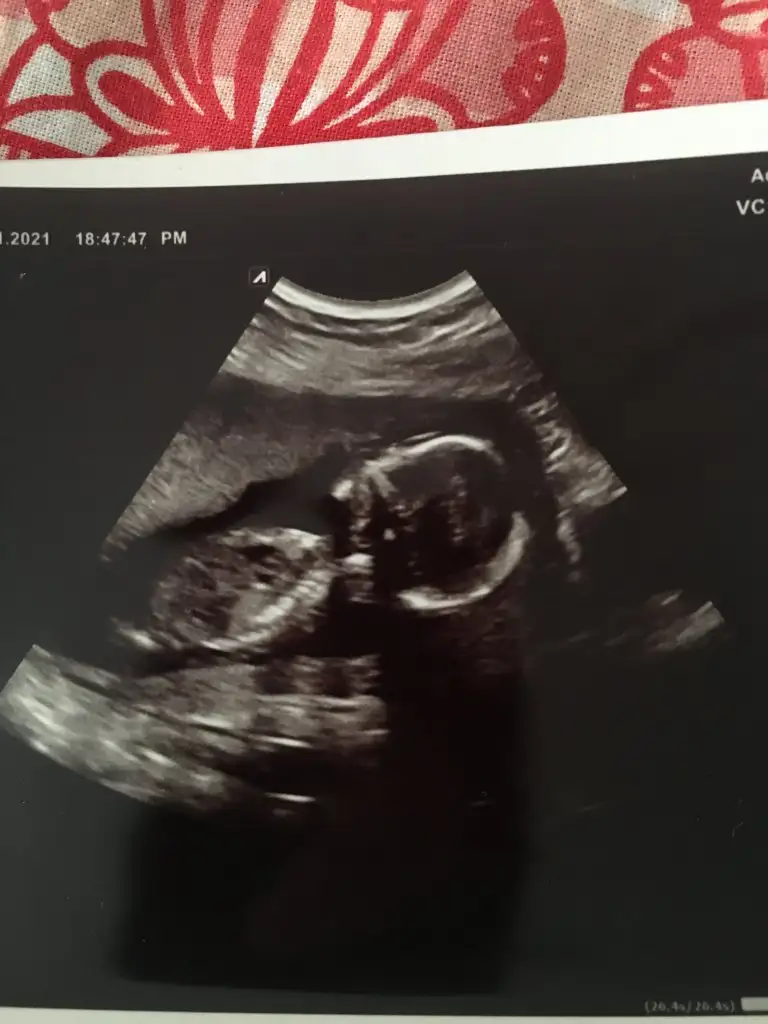

Banada tahmin bulunurmusunuz

Eklentiler

• 7D90F576-1F37-4336-B08E-CCB7B86A97B3.webp

7D90F576-1F37-4336-B08E-CCB7B86A97B3.webp

32,3 KB · Görüntüleme: 69